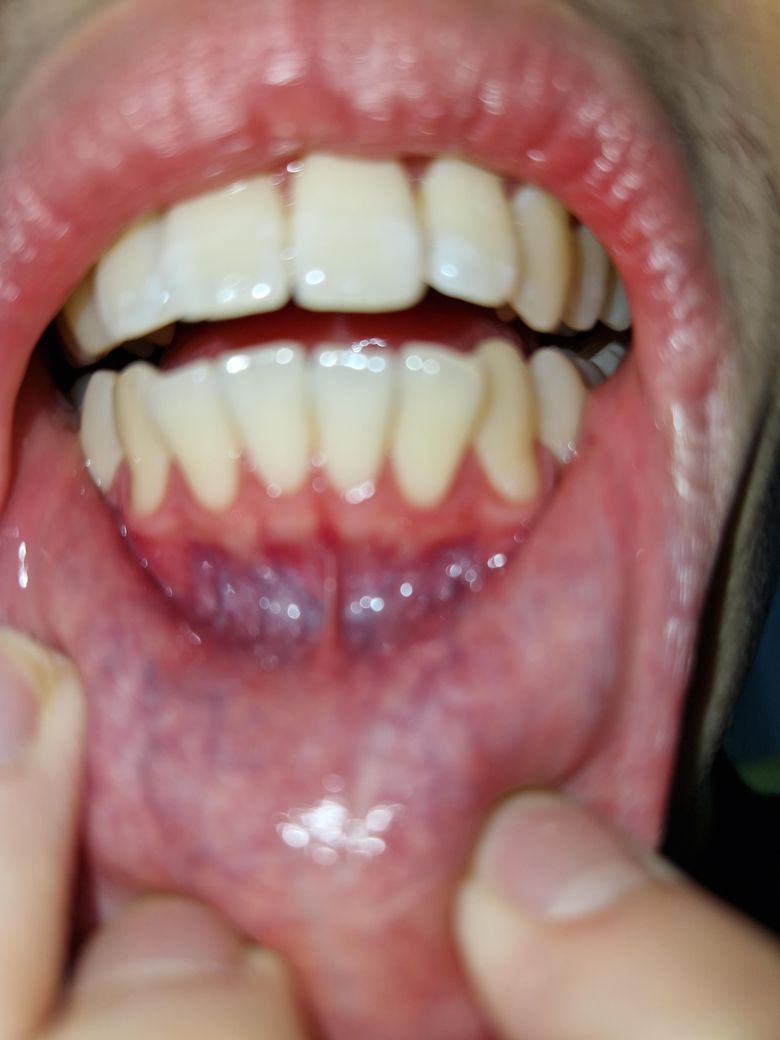

송곳니 잇몸이 많이 내려간건지 궁금합니다

송곳니 쪽 잇몸이 많이 내려간 것 같아요. 이빨이 흔들리거나 그러지는 않는데 내려간게 맞는지 아닌지, 맞다면

평소 관리만 잘 하면 되는지, 아니면 치료가 필요한 정도인지 궁금합니다.

• 1번 째 사진

잇몸의 퇴축이 약간 관찰되고 있지만 그렇게 걱정할 정도는 아닙니다. 앞으로 관리잘해주시면 됩니다.

현재 잇몸 퇴축이 다소 있으나, 심하지는 않습니다. 아직은 치료가 필요로 되는 정도는 아니며, 평소에 양치질을 할때 너무 강하게 하지 말고 부드럽게 양치질을 하여관리하고, 칫솔도 부드러운모를 사용하길 권합니다.

노화로 인해 잇몸이 내려가는 것은 자연스러운 현상입니다.

만약 시리고 불편감이 있는 경우에는 치과에 방문하여 진료를 받길 권합니다.

치아가 난 방향에 따라서 잇몸은 내려갈 수도 있습니다. 또한 양치질을 너무 세게 했다면 잇몸에 자극이 되어 잇몸이 내려가는 경우도 있습니다.

양치질을 할 때 잇몸을 무리하게 자극하지 않는 것이 좋습니다. 큰 문제는 없는 것으로 보이나 걱정이 되신다면 치과에서 진료를 받아 보는 것을 권유 드립니다.

잇몸이 많이 내려간것같진 않지만 잇몸이 전체적으로 많이 부어 잇는상태같으니 치과에 가셔서 스켈링 및 잇몸치료를 받아보세요.